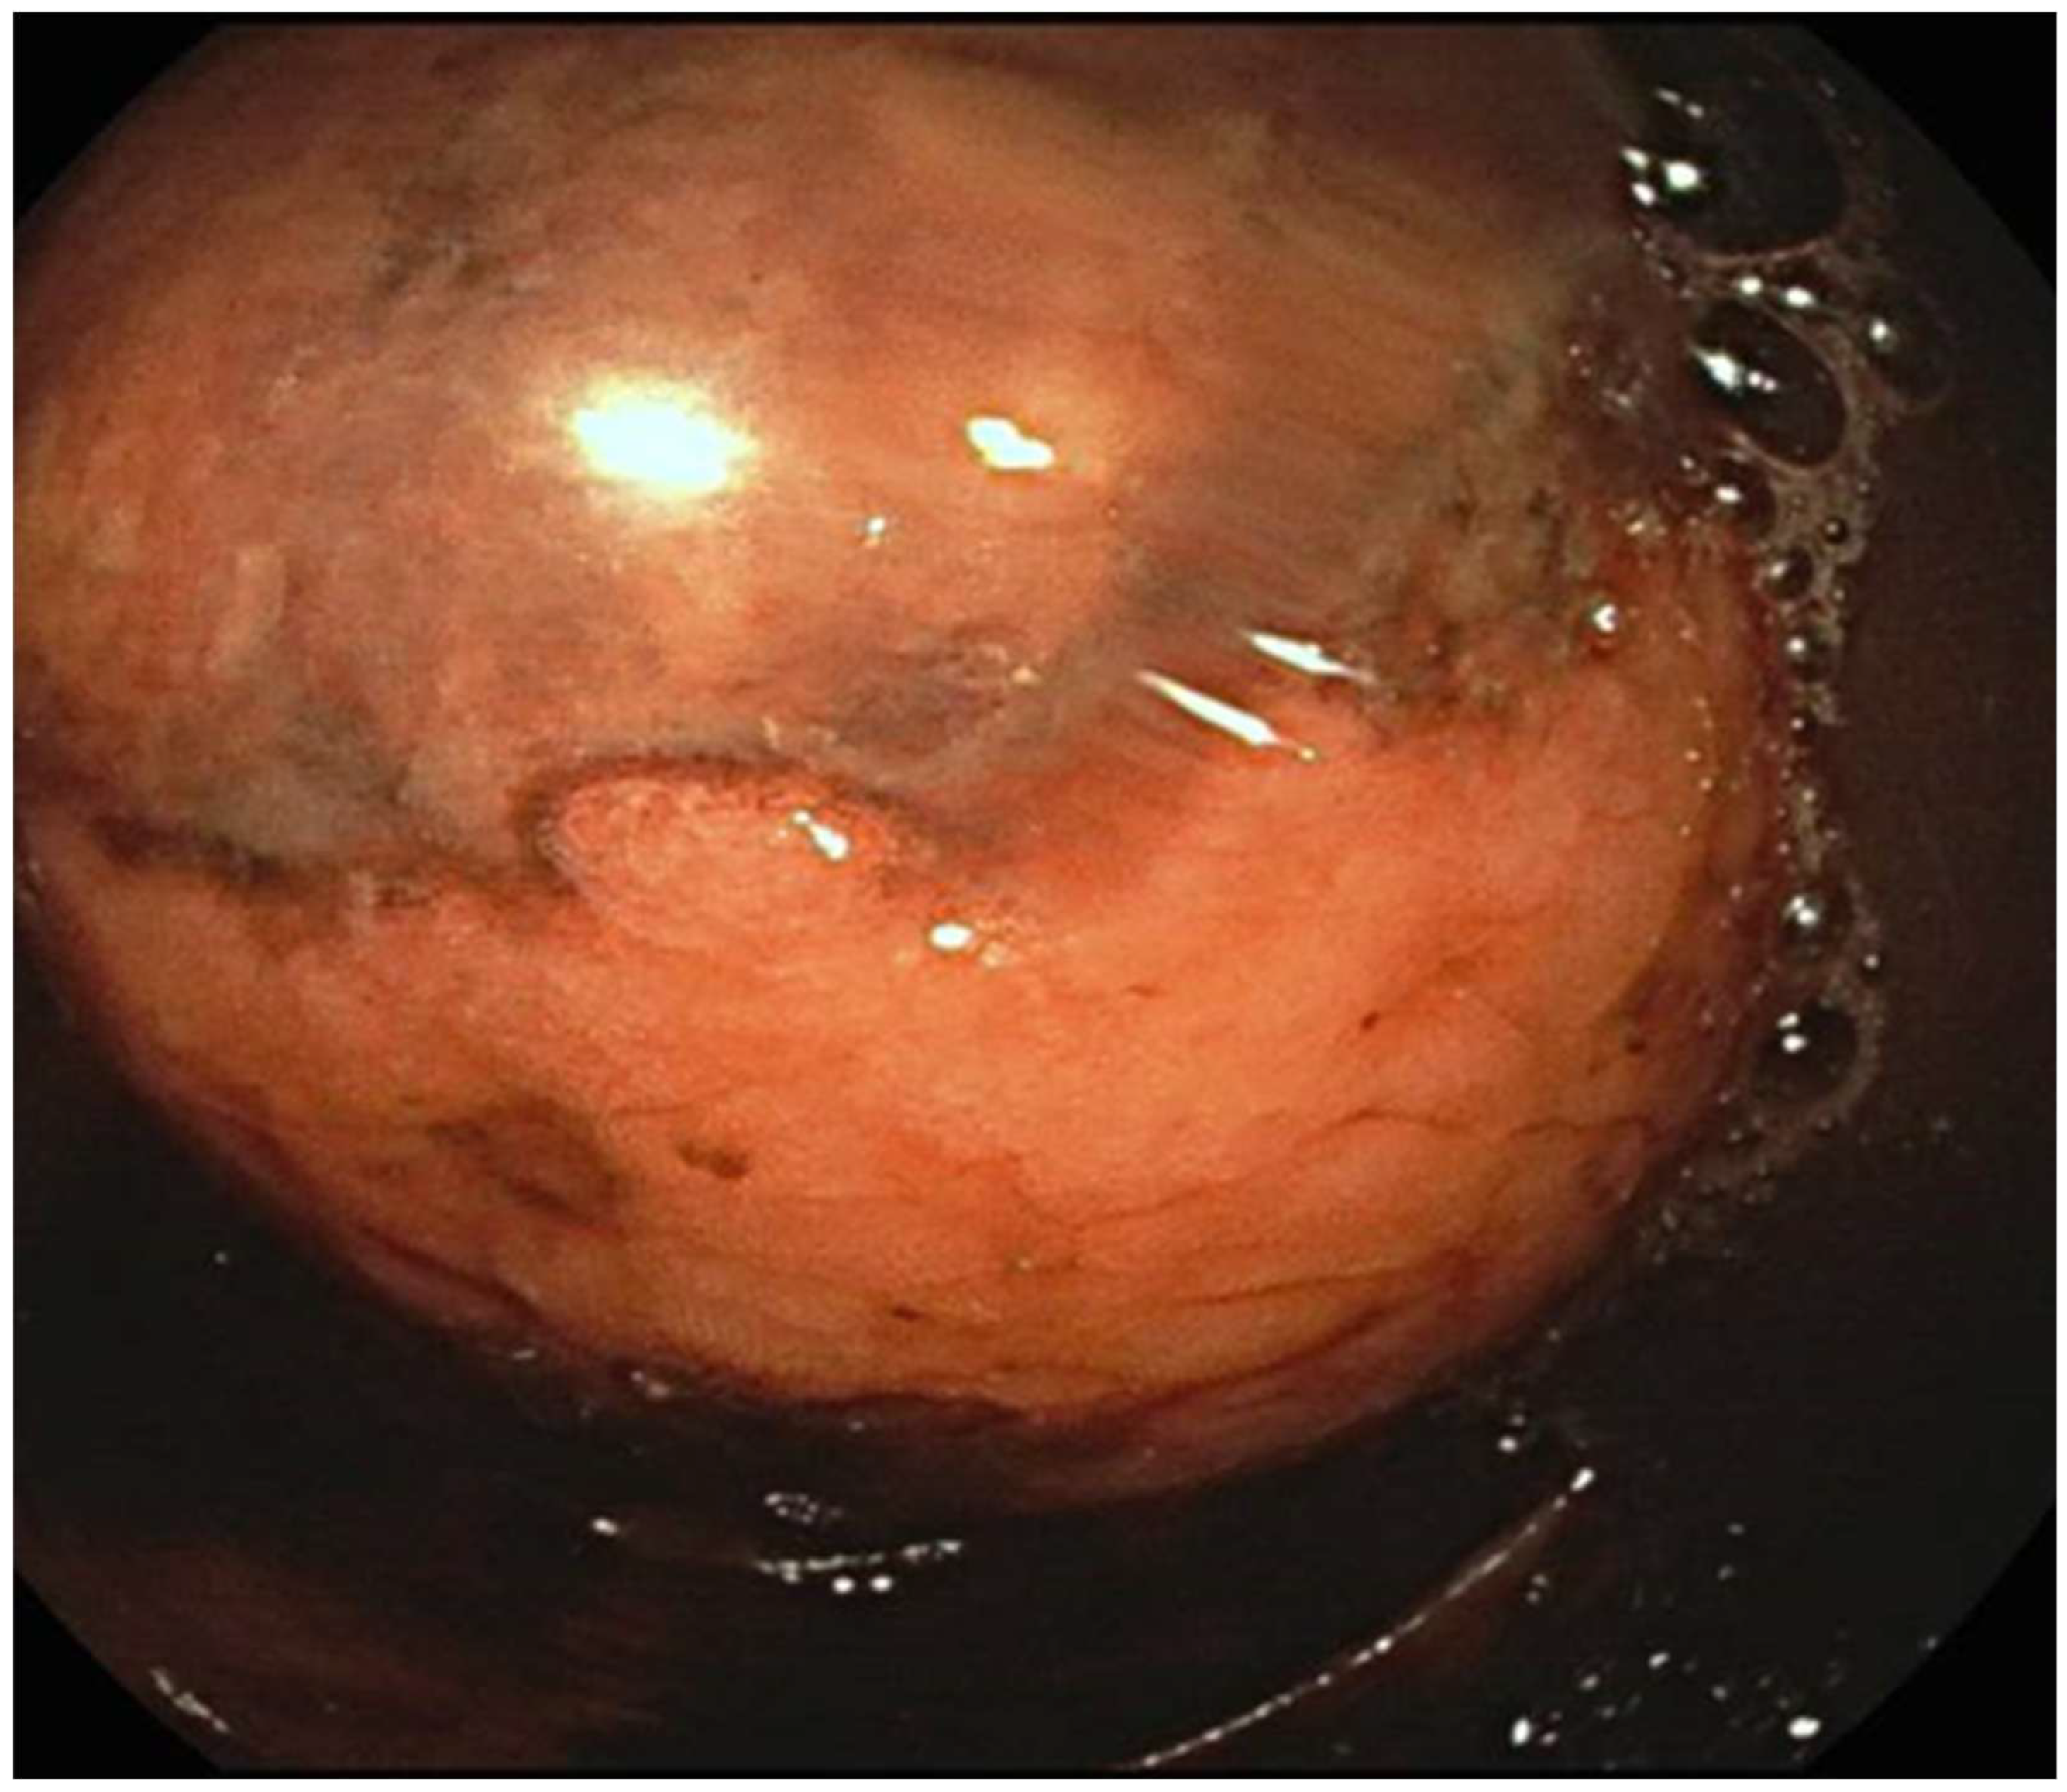

2.4. Endoscopic Techniques